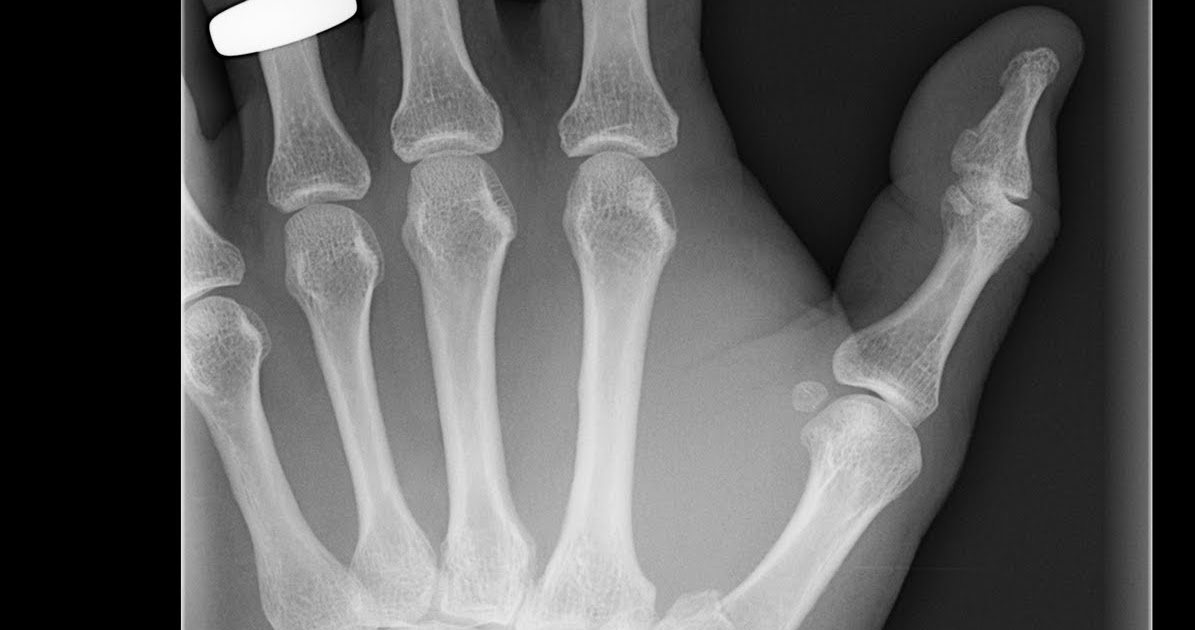

Bennett's Fracture X Ray . traction radiography may be used to assess the degree of comminution in appropriate fractures (eg, bennett, rolando,. a bennett fracture is a fracture of the articular surface in the base of first metacarpal bone and is considered as an unstable fracture. They need to be distinguished from epibasal. determining the optimal treatment method for bennett’s fractures remain a challenge and has been the subject. the bennett fracture is the most common fracture involving the base of the thumb. It is important to distinguish it. a bennett fracture is a fracture of the base of the thumb resulting from forced abduction of the first metacarpal. This fracture refers to an intraarticular fracture that separates the palmar.